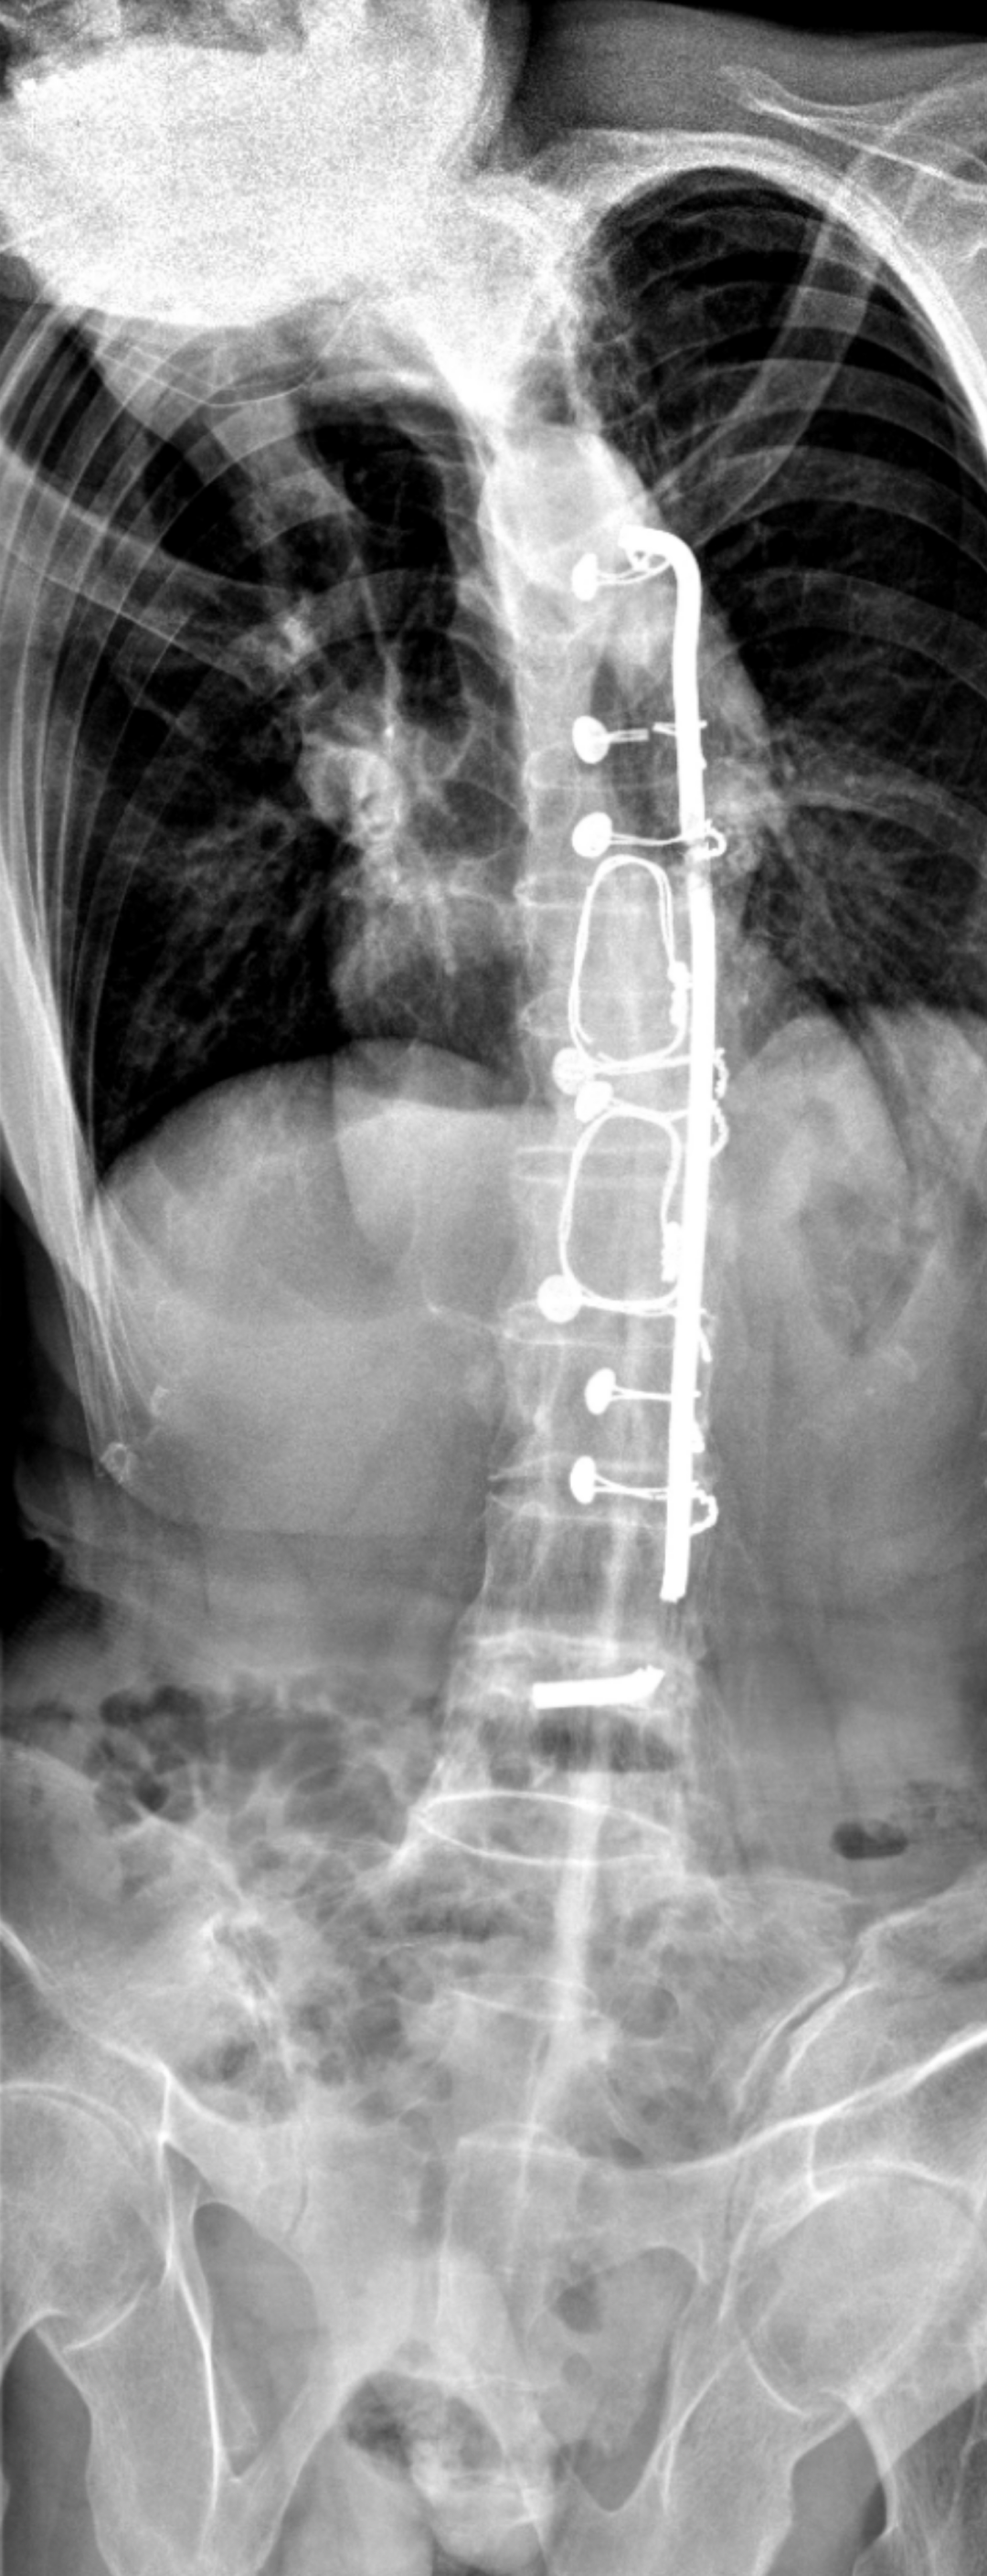

术前拍片(图源:骨一科)

多年的强直性脊柱炎,脊柱的竹节样改变的是脊柱骨犹如一根细长的玻璃棒,轻微的不当外力都有可能导致其骨折。结合陈伯的脊柱外形,医护人员利用体位垫和五床棉被,垒成一座弧形的“小山”,再由六位医护人员小心翼翼的帮他翻身过床,摆成术中的俯卧体位。